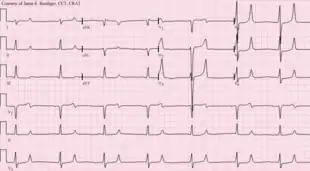

- Potassium accumulates in the blood (hyperkalemia with a range of symptoms including malaise and potentially fatal cardiac arrhythmias). Hyperkalemia usually does not develop until the glomerular filtration rate falls to less than 20–25 mL/min/1.73 m2, when the kidneys have decreased ability to excrete potassium. Hyperkalemia in CKD can be exacerbated by acidemia (which leads to extracellular shift of potassium) and from lack of insulin.[25]